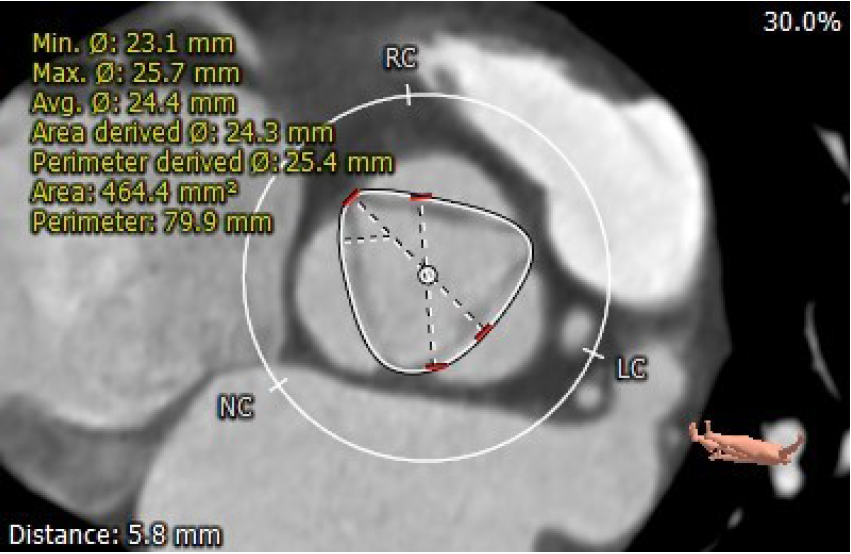

术前CT评估

1.患者主动脉瓣三叶式,瓣叶基本等大,瓣叶增厚,瓣叶游离缘密度稍高,无冠窦壁轻微钙化;

2.患者主动脉瓣环周长折算直径约23.2mm;

主动脉瓣环周长折算内径:23.2mm

距瓣环5.8mm处瓣叶开放最大直径25.4mm

左室流出道周长折算内径约24.3mm